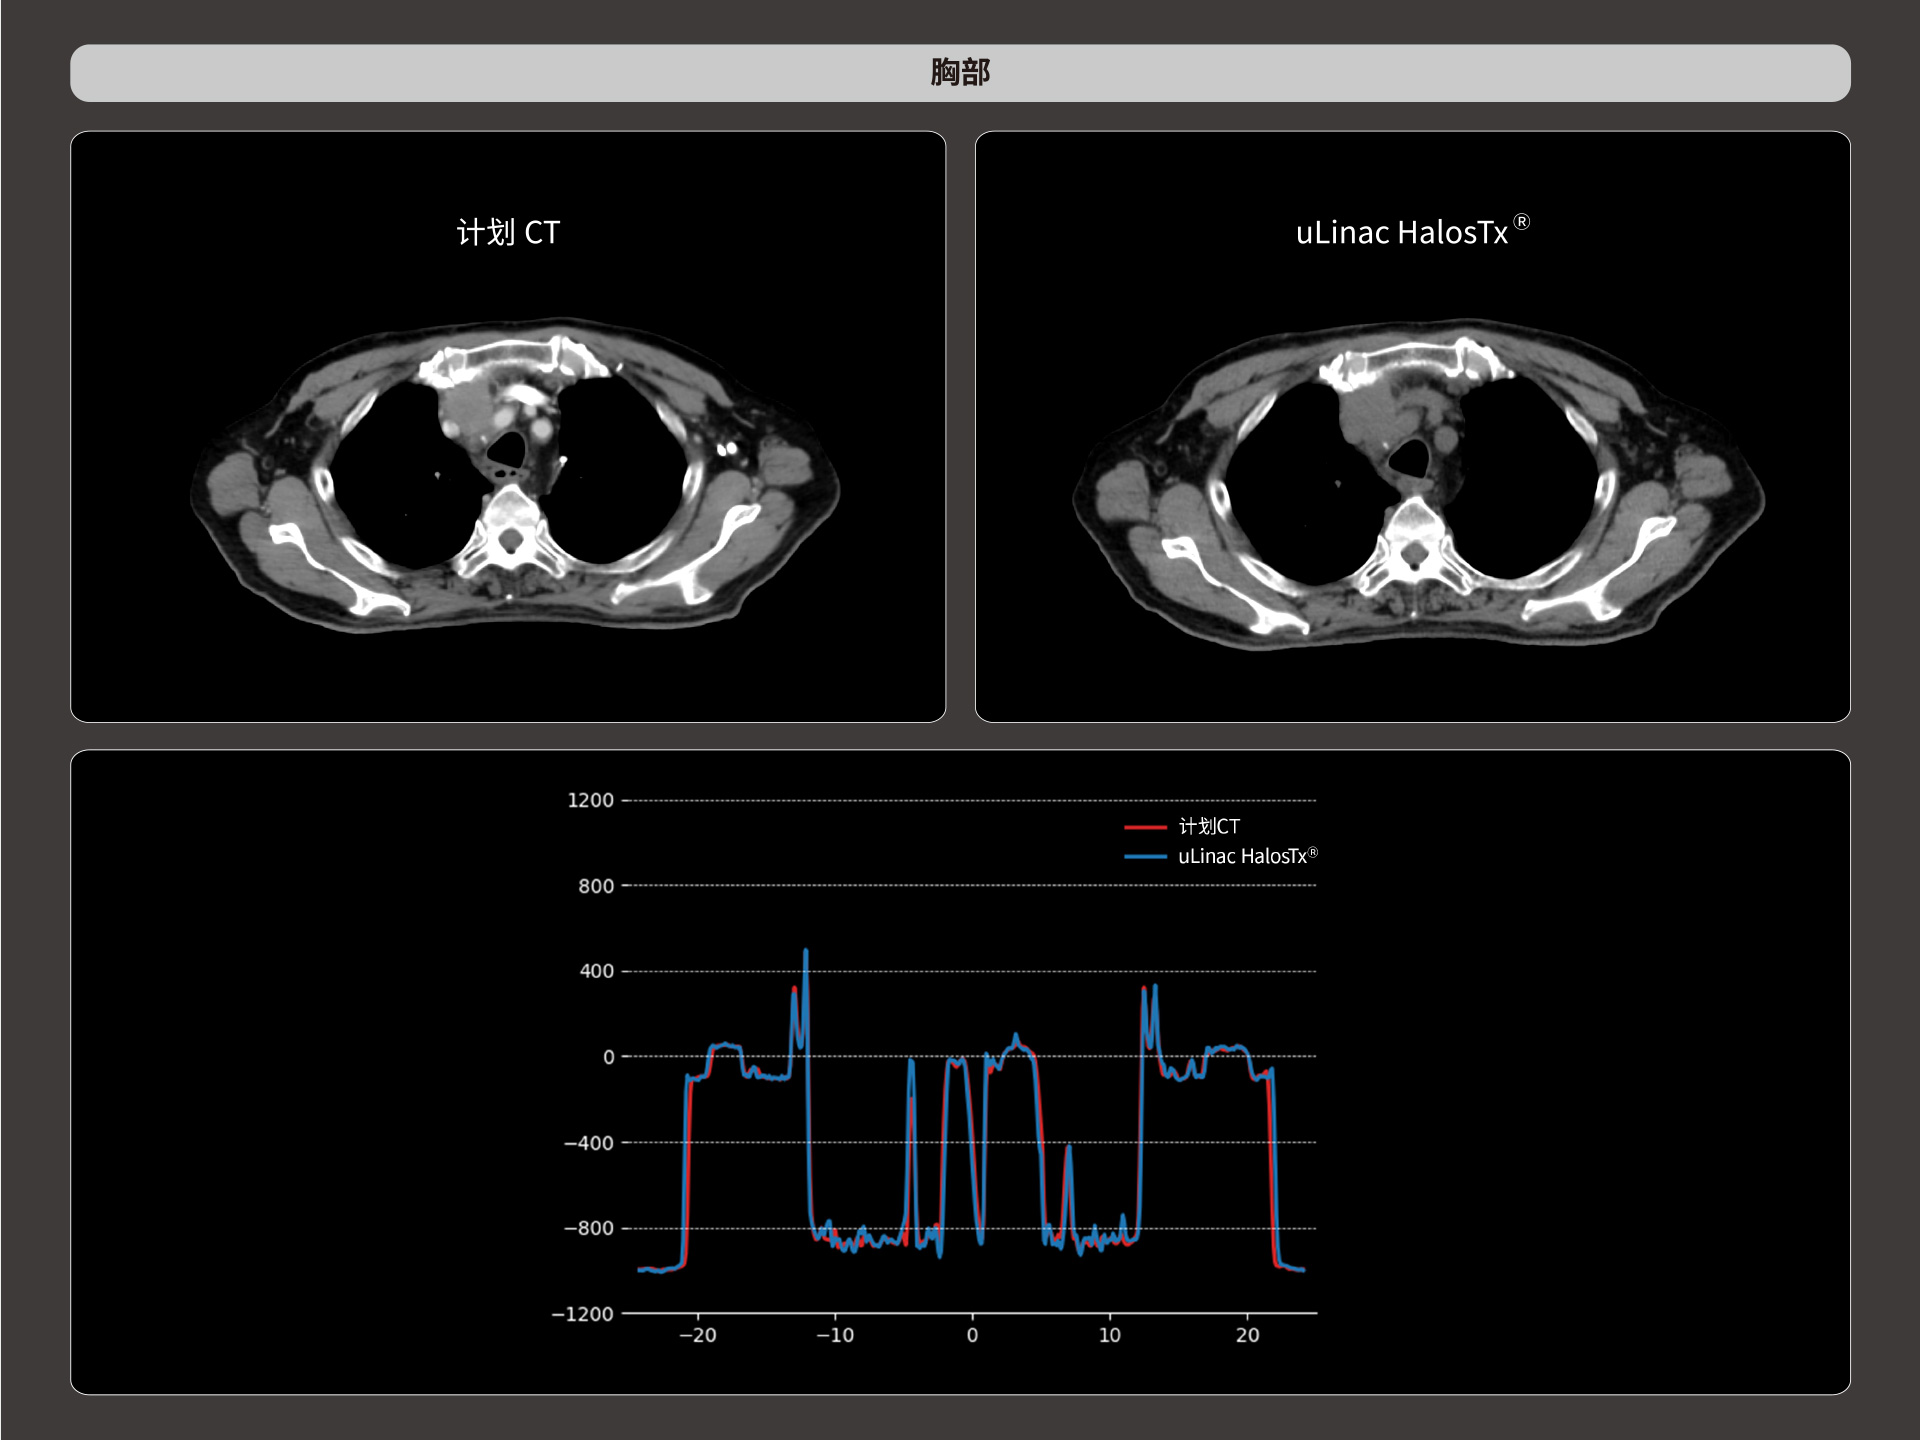

标准视野 63cm,避免扫描信息缺失

全景视野

87cm CT影像孔径设计适配多种摆位姿势,兼顾不同体型患者